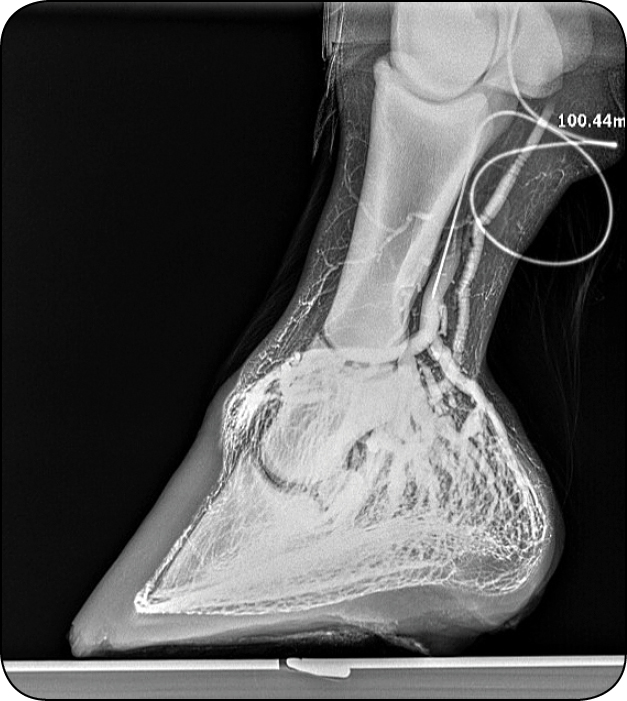

Końcówka wenflonu powinna zostać umieszczona pod bandażem kohezyjnym, a wykonanie serii zdjęć RTG należy rozpocząć natychmiast. Czas odgrywa w procedurze kluczową rolę. Środek kontrastowy bardzo szybko przemieszcza się poza światło naczyń, dlatego należy podać go możliwie najszybciej. Wszystkie zalecane zdjęcia powinny zostać wykonane w ciągu 60-90 sekund od momentu iniekcji.

Rekomendowana kolejność projekcji:

- boczne z obciążeniem,

- AP (przednio-tylne) z obciążeniem,

- boczne bez obciążenia (kończyna nie powinna mieć kontaktu z podłożem),

- AP bez obciążenia,

- boczne ponownie obciążone (ang. late loaded),

- AP ponownie obciążone,

- projekcja stawu pęcinowego – kontrola skuteczności stazy.